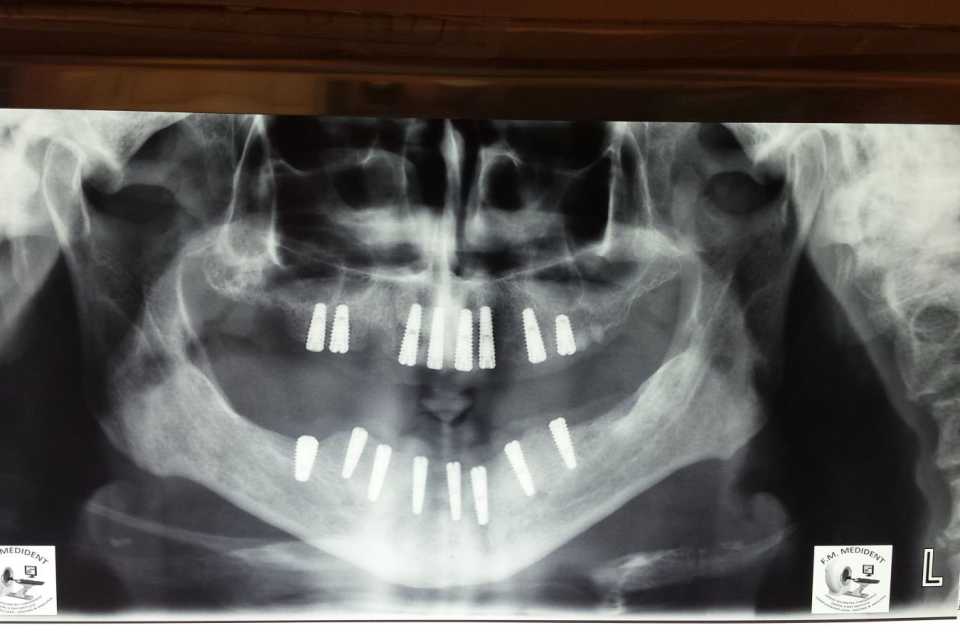

Pacientul s-a prezentat în cabinet cu o edentație totală bimaxilară. Au fost inserate 8 implanturi la maxilar și 8 implanturi la mandibulă. După perioada de osteointegrare au fost făcute două punți totale metalo-ceramice (ceramica Ivoclar D'sign).